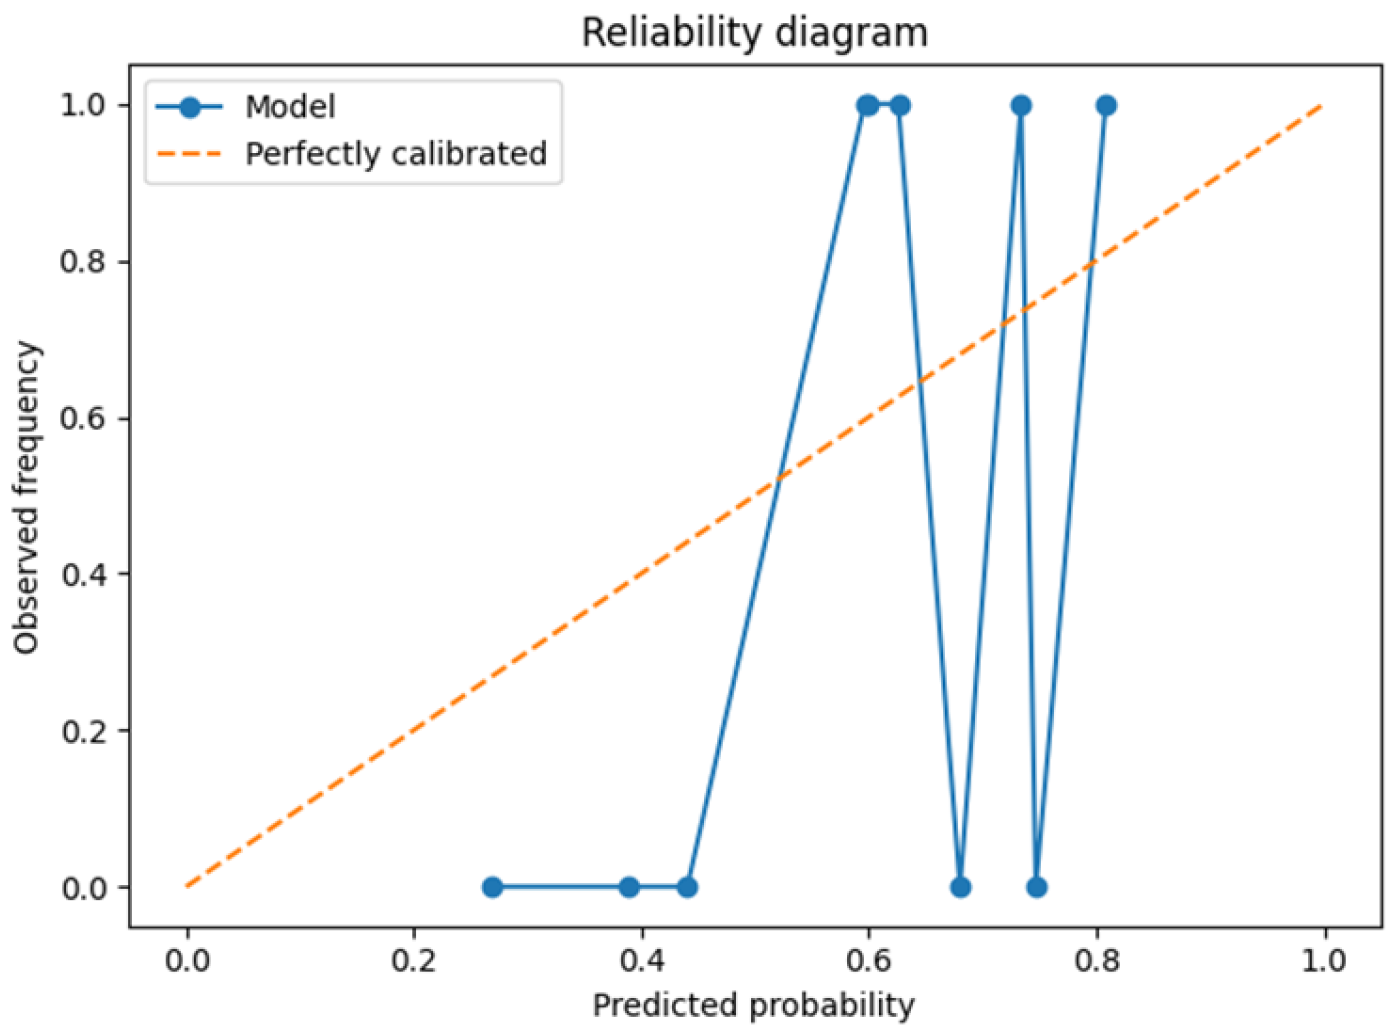

3.1. Leave-One-Patient-Out Cross-Validation (LOPO-CV)

| Brier score | 0.18 ± 0.05 | – |